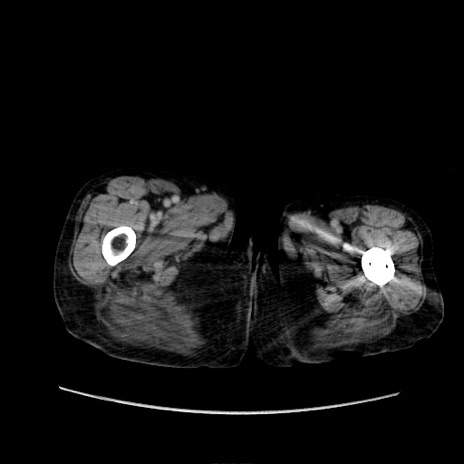

症例31(横断像)

【症例】80歳代 女性

【主訴】腹部膨満感

【現病歴】他院にて肝硬変にてフォロー中。1週間前から便秘、腹部膨満感、臍部腫瘤あり受診となる。

【既往歴】肝硬変

【身体所見】腹部膨隆あり、皮膚変化なし、疼痛なし。

【データ】WBC 4600、CRP 0.25